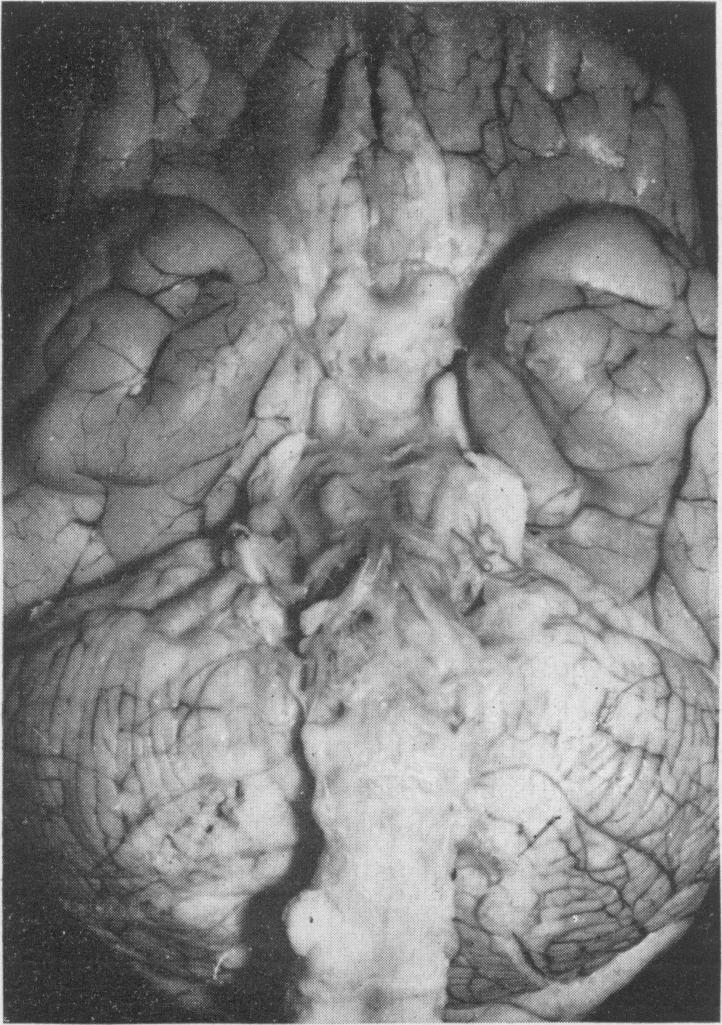

The clinical and pathological features of 63 cases of post-mortem-proved diffuse infiltration of the leptomeninges by tumour are presented. A wide variety of tumours of the nervous system, both primary and secondary, was found to give rise to such involvement, with adenocarcinoma having a particular propensity to behave in this manner. Dysfunction of cranial and spinal nerves, a confusional state and headache were prominent clinical features. Examination of the cerebro-spinal fluid was found to be less useful diagnostically in cases of primary tumours of the nervous system with leptomeningeal involvement than in cases of diffuse infiltration of the meninges by carcinoma.